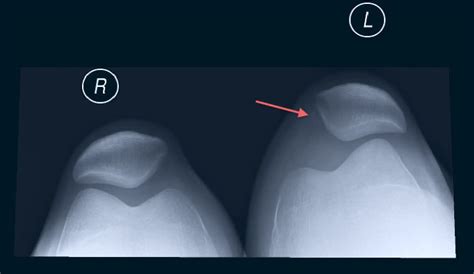

Diagnostic Procedures and Clinical Assessment

Physicians typically diagnose this condition through a combination of physical examination and imaging. During the exam, a doctor may perform the “Apprehension Test,” where they gently push the kneecap laterally while the knee is bent. If this causes the patient to feel like the kneecap is going to slide out—or causes genuine discomfort—the test is positive for instability.

X-ray To identify bone spurs, fractures, or structural anatomy of the trochlear groove.

• lateral patellar dislocation x ray

• lateral patella subluxation radiology